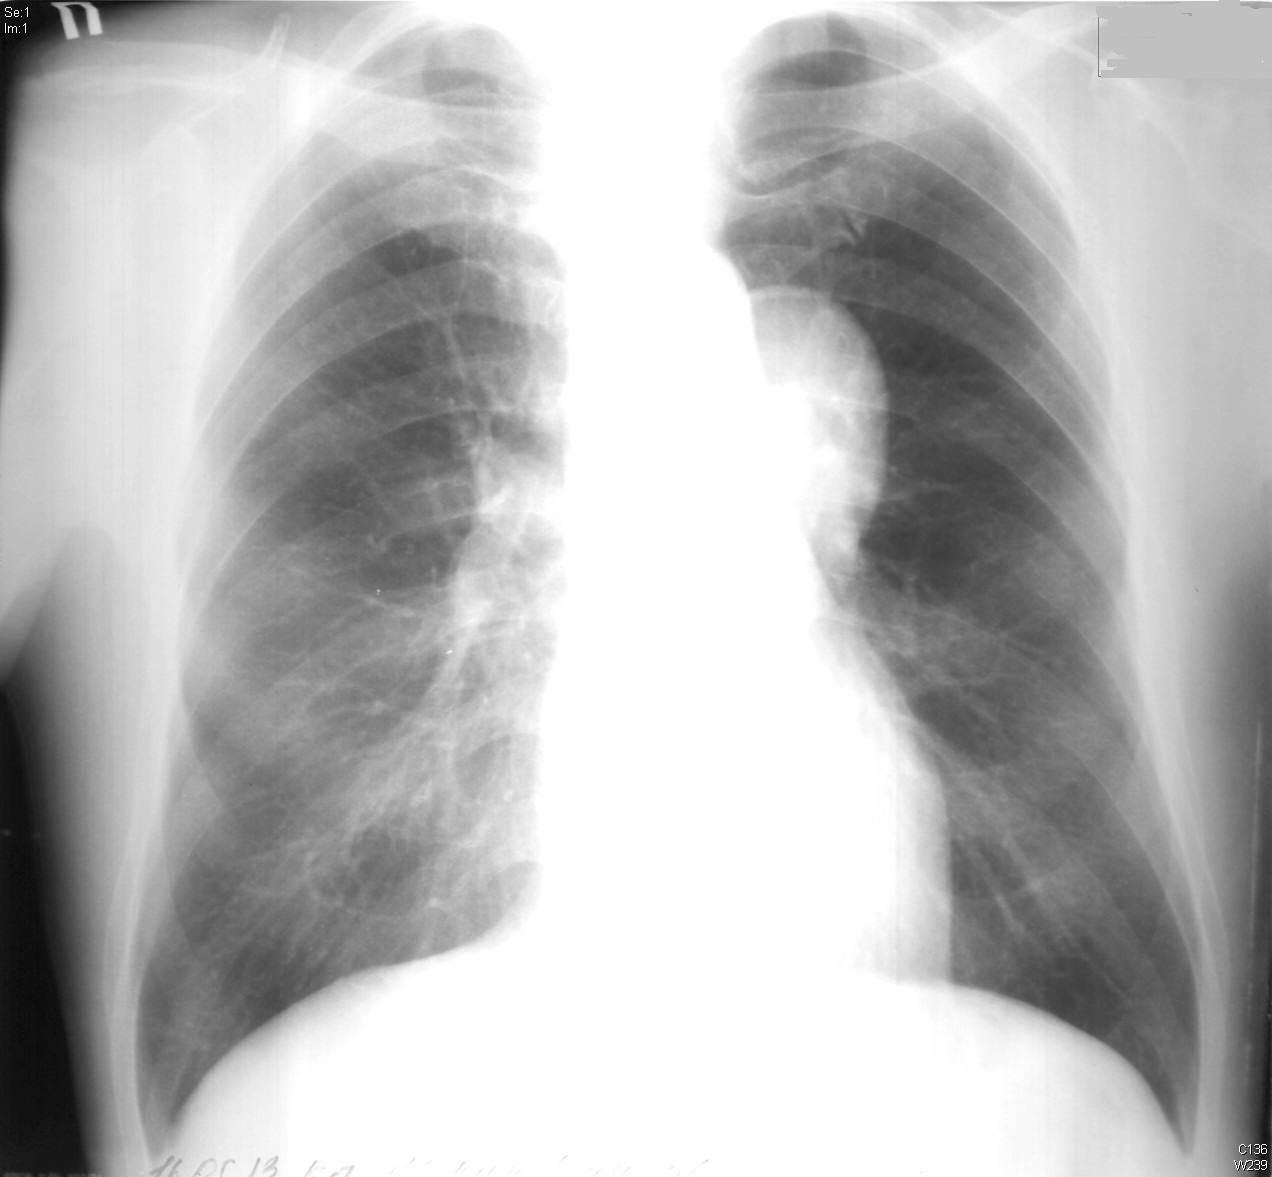

M/56

4°³¿ù ÀüºÎÅÍ ¹ß»ýÇÑ Èí±â½ÃÀÇ ÈäÅë

±âħ °¡·¡ ÀÖÀ½

5ÀÏ ÀüºÎÅÍ ¾ÇÈ­µÇ¾î ³»¿øÇÔ

2012³â 11¿ù Chest PA, lateral

2013³â 5¿ù Chest PA, lateral ÀÔ´Ï´Ù.